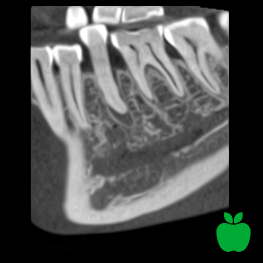

Normalna rozdzielczość

wielkość woksela 200 μm, dawka pacjenta ~86 μSv

Duża szczegółowość, średnia dawka